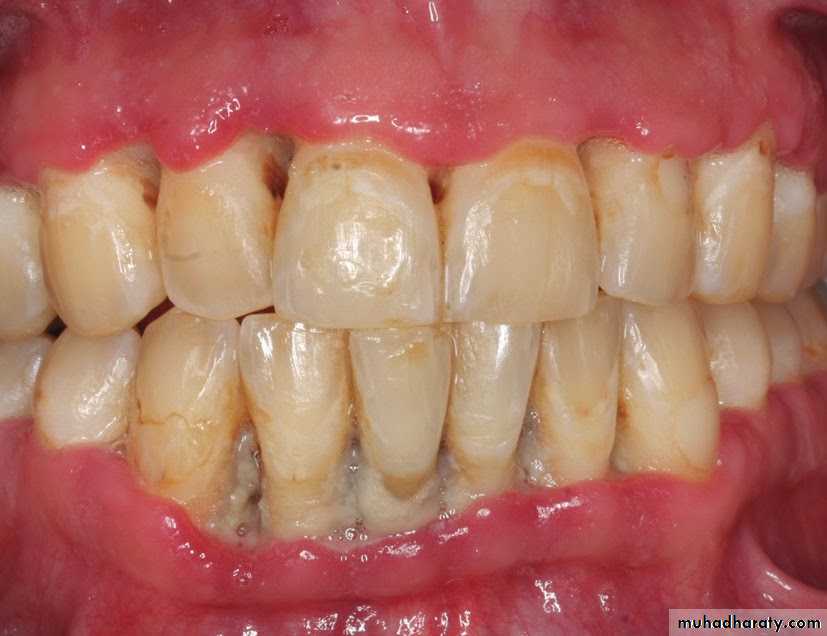

• NG – an inflammatory destructive gingival condition, characterized :byulcerated and necrotic papilla and gingival margins. Punched out crater like depressions at the crest of the interdental papillae is a characteristic Feature

• The surface of the craters is covered by a gray pseudomembranous

slough. The sloughed material has little coherence and is composed of

fibrin, necrotic tissue, RBC,WBC, Bacteria.

• Linear erythema demarcating marginal necrosis and the relatively

unaffected zone

• In some cases the lesions are denuded of the surface

pseudomembrane, exposing the gingival margin which is red, shiny, &

hemorrhagic. The characteristic lesion may progressively destroy the

gingiva & underlying periodontal tissues.

• Spontaneous gingival hemorrhage or pronounced bleeding after the slight stimulation are characteristic clinical signs.